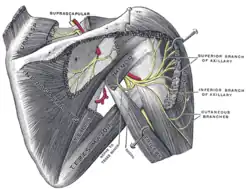

Suprascapular e nervos axiliares do lado direito, vistos de trás.

Suprascapular e nervos axiliares do lado direito, vistos de trás. -